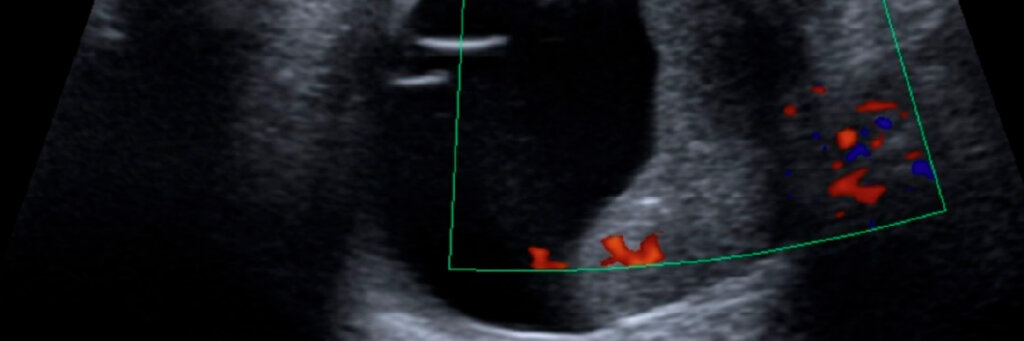

A ultrassonografia ocular é um exame de imagem indolor e não invasivo que utiliza ondas sonoras para formar imagens do interior do globo ocular.

É especialmente útil quando a visão está comprometida por opacidades (ex: catarata, hemorragias), impedindo a visualização direta da retina.

No Médicos de Olhos, esse exame é realizado com aparelhos de alta resolução e interpretação por especialistas.